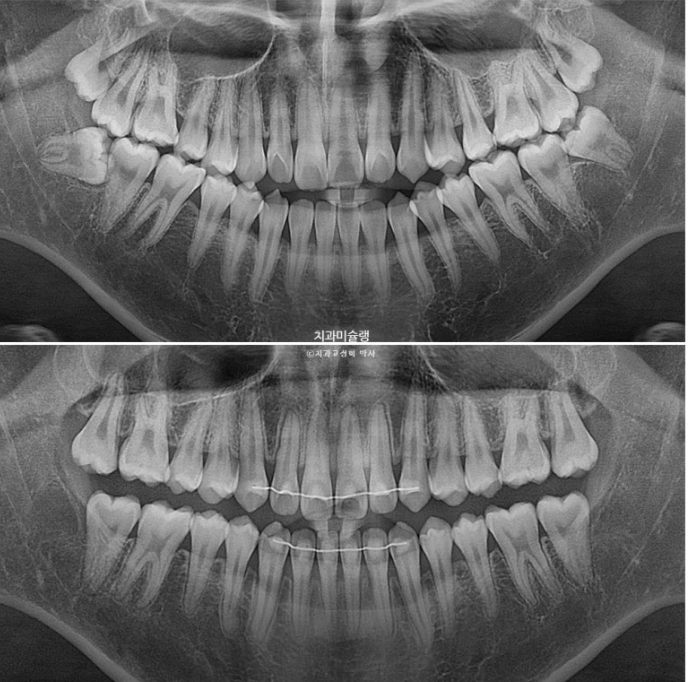

치료계획은 아래 사랑니 2개를 발치하고 사랑니 공간으로 치열을 뒤로 미는 것 입니다.

아래 어금니들은 가용한 사랑니 공간을 최대한 이용하며 뒤로 들어갔습니다.

2년 반동안 치근흡수도 없고 치근평행도는 좋습니다.